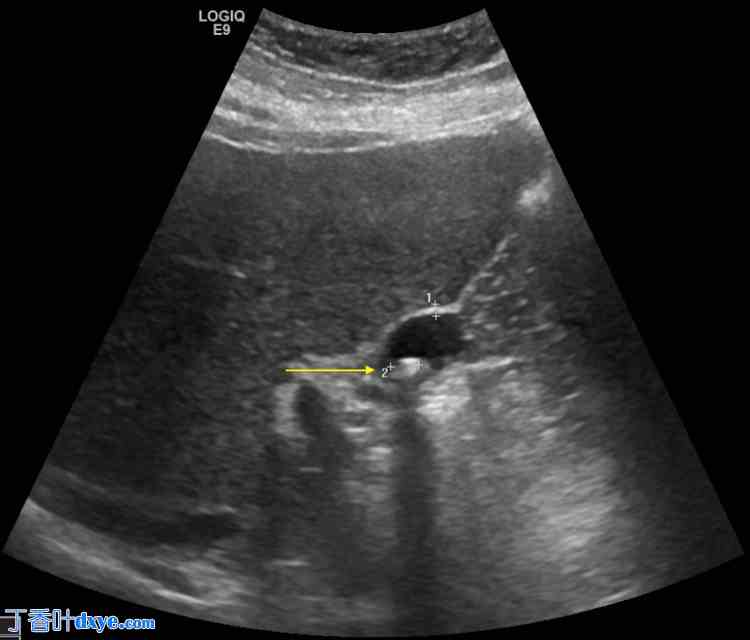

一名39岁女性患者,因反复出现右上腹(RUQ)疼痛、恶心和呕吐,于2013年接受胆囊切除术,现于院就诊,拟行胆囊切除术。患者自述自首次手术以来,一直感觉不适,右上腹疼痛持续放射至背部。尽管患者此前已接受胆囊切除术(图1),但在超声检查发现胆结石后,其初级保健医生(PCP)将其转诊至院外科团队。患者既往病史提示为糖尿病前期,末次糖化血红蛋白(A1c)为5.9%,肥胖(BMI为37.6 kg/m²),伴有高血压,但未确诊其他外科手术史。近期所有实验室检查值均在正常范围内。

图 1. 右上腹超声检查显示胆囊残余,壁厚 1 毫米,并存在约 2 毫米的胆结石(黄色箭头)。可见多处结石阴影。

胆囊周围未见积液。超声墨菲征阴性。